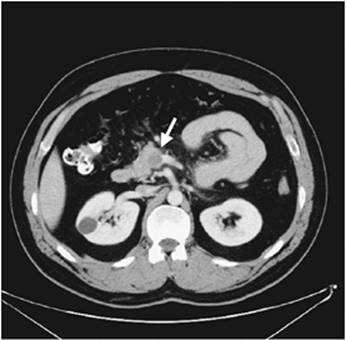

CT arteriography has largely replaced catheter-based contrast arteriography as the diagnostic study of choice for patients with CMI (Fig. 159.2) and is usually sufficient to plan open surgical revascularization (16,17,18). CT arteriography is safe, noninvasive, and almost universally available. It is very good for identifying occlusive disease in the superior mesenteric artery and celiac axis. Furthermore, it is useful for identifying the presence of collateral vessels between the visceral vessels (i.e., celiac axis, superior mesenteric, inferior mesenteric) and/or the internal iliac arteries that suggest hemodynamically significant stenoses. Additionally, it is very good for evaluating other intra-abdominal processes.

Figure 159.2. Two CT arteriograms are shown in a patient with chronic mesenteric ischemia (CMI) and an occluded celiac axis and superior mesenteric artery. A: The origin of the superior mesenteric artery is shown with the arrow. There is no contrast within the lumen of the vessel at this cross section. B: The superior mesenteric artery is shown with the arrow in this cross section that is 10 mm caudal to the first image. The artery is patent at this level as reflected by the contrast within the lumen.